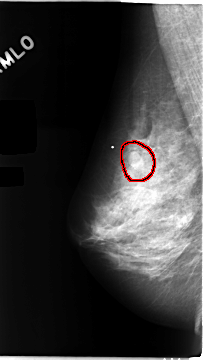

C_0104_1.RIGHT_CC

RIGHT_CC LINES 4688 PIXELS_PER_LINE 2592 BITS_PER_PIXEL 12 RESOLUTION 50 OVERLAY

FILE: C_0104_1.RIGHT_CC.OVERLAY

TOTAL_ABNORMALITIES 1

ABNORMALITY 1

LESION_TYPE MASS SHAPE OVAL MARGINS CIRCUMSCRIBED

ASSESSMENT 3

SUBTLETY 5

PATHOLOGY BENIGN

TOTAL_OUTLINES 1

BOUNDARY